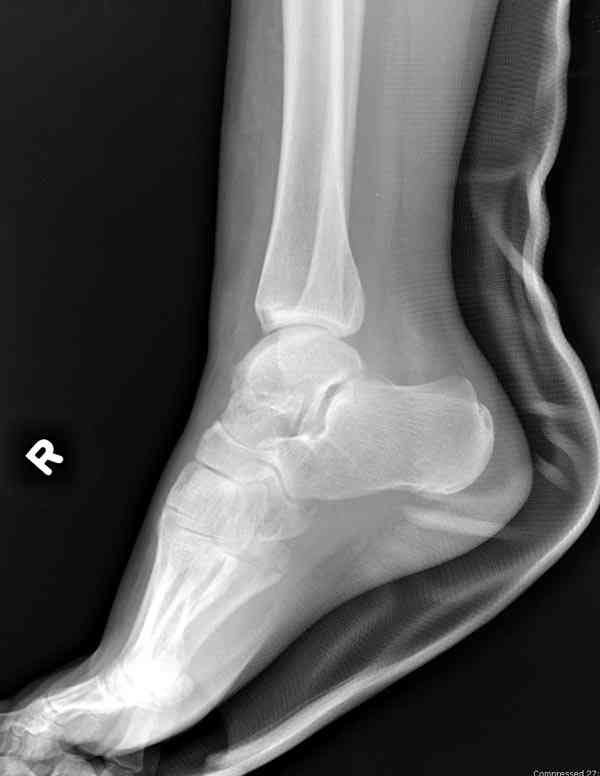

И второй случай из недавней ташкентской практики, (извините за качество ренгенограммы и только в одной проекции) случай падения с высоты (кстати моего друга - известного киноактера) - открытый

смещенный перелом тарана, с переломом переднего края дистального эпиметафиза большеберцовой кости.

При поступлении в приемной сделана первичная обработка с ушиванием открытой латеральной раны и вытяжением за пятку.

Из-за отсутствия времени пришлось оперировать на второе утро, из материала, что имеем на месте, фиксирован двумя шурупами, а третий-это контур сломанного жойстика в 4 мм. На дистальный медиальный конец тибиа antiglide 3.5 мм пластина. Через пару дней выписан и несмотря на предупреждение, самостоятельно начал нагрузку в 4 недели, время не ждет, снимается в боевике в Росийской Федерации.